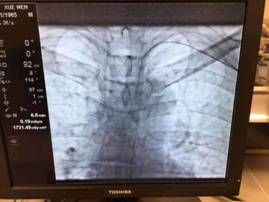

如何解决肝癌介入术后的这个“老大难”问题也成为介入团队的攻关目标之一,团队通过反复查阅文献和与国内外同行的广泛交流学习,发现通过手部的桡动脉穿刺,即可有效解决左某的顾虑。但该途径的穿刺血管很细,穿刺成功率低;最难的地方还在于这种治疗路径与传统治疗路径完全相反,对医生的操作技巧要求极高。为此,介入团队医生们将该手术难点逐一分解攻破并反复演练,于10月31日由游科医师主刀,为左某从桡动脉入路行肝动脉化疗栓塞术。一个半小时后,左某自己走下手术床并步行回到肝胆外科病房,于11月1日出院回家。

桡动脉入路行肝动脉化疗栓塞术这一技术突破,进一步实现了肝癌患者治疗的微创化,充分体现了加速康复外科理念。在重庆市肝胆外科首席专家工作室领衔专家龚建平主任领导下,重医大附二院肝胆外科始终坚持以技术求发展。目前为止,除开展肝癌介入栓塞外,今年介入团队在组长刘作金教授带领下,已成功开展门静脉癌栓放射粒子及支架植入、布—加氏综合征、肝硬化上消化道大出血TIPS治疗、肝癌栓塞分期腹腔镜切除等新技术。

改良后的TACE术——经桡动脉入路

通过手部的桡动脉穿刺插管至肝动脉,在目标血管处栓塞、注射栓塞剂。其相较于经股动脉入路,有以下优点: